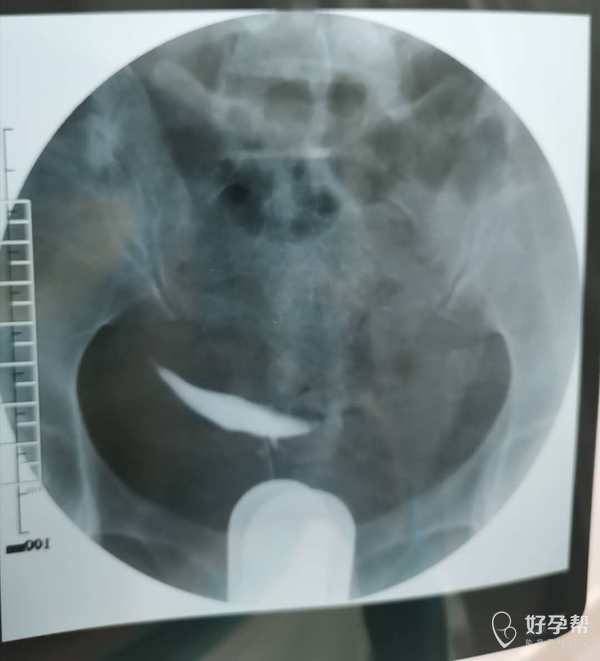

我这个是做了输卵管介入手术,请问输卵管是通了

你的片子提示双侧输卵管不通,未孕4年,合并腺肌症和腺肌瘤,建议你直接试管婴儿助孕。试管前不需要宫腹腔镜检查。